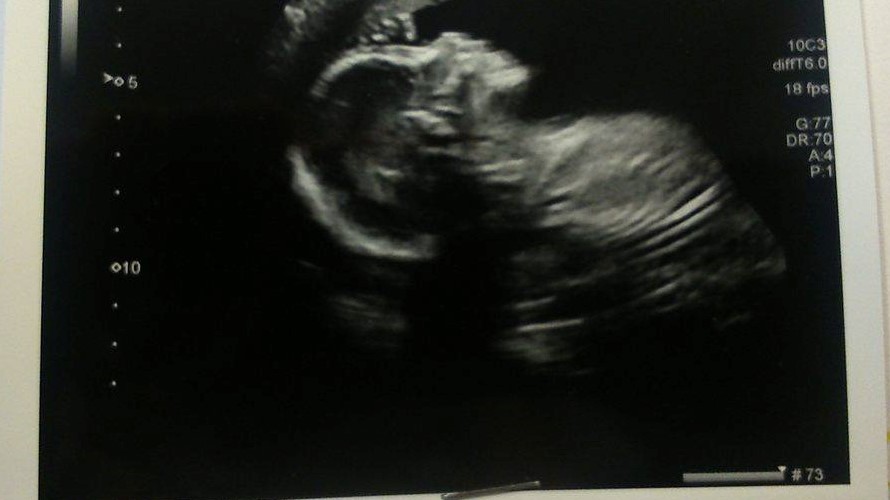

Please. Any guesses on a boy or girl please? Skull/Nub Theory?

Are there any signs at all in my scan photos about whether I'm carrying a boy or a girl?

I know they aren't the clearest photos, but they're the only ones I have.

20 weeks

Attachment 36257

Boy lean.